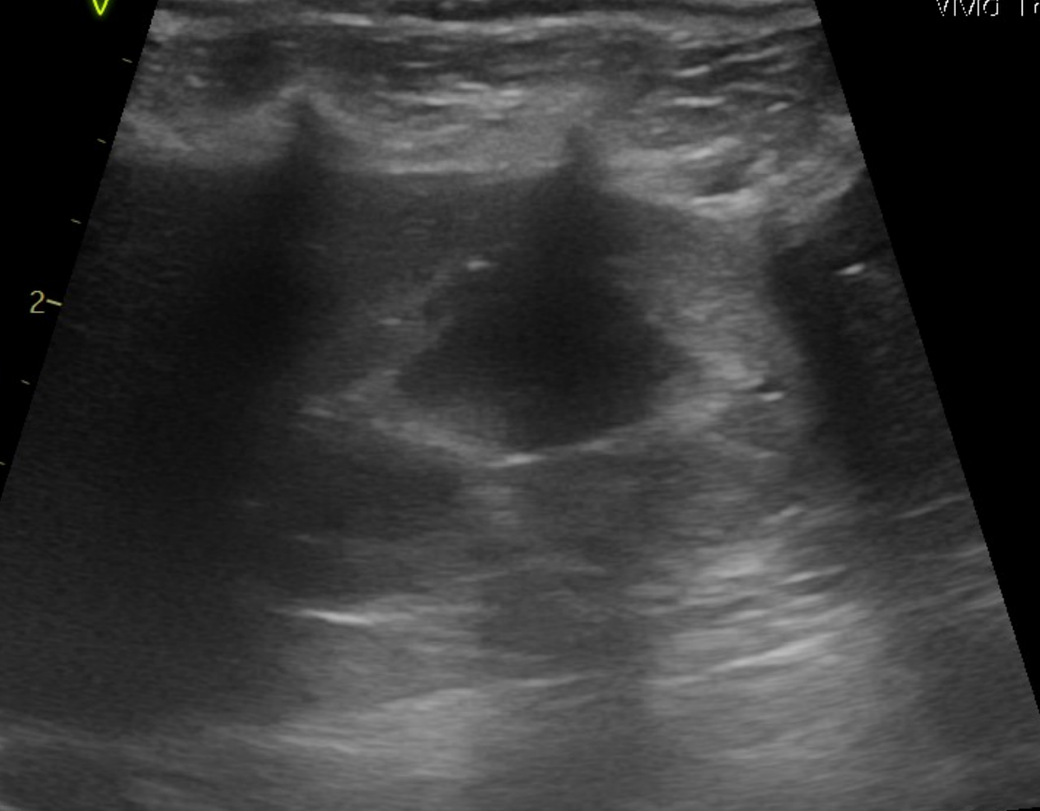

강아지 신장결석 종류 모양만으로는 판단이 안되나요? 소변에선 크리스탈이 발견된게 없다고 합니다

모양만으로 추측 조차 할수가 없는건가요? 한번 봐주시면 감사하겠습니다.

예, 없습니다. 결석이 매우 커진 상태 (몇센치미터 크기 정도)로 커졌을때나 일부 추정되지만 겉면과 내부 코어의 씨앗의 성분은 별도라 이때는 또 성분검사를 해야 하는정도로 부정확합니다.